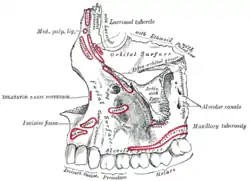

Mouth (oral cavity) Left maxilla. Outer surface.

Left maxilla. Outer surface. Base of skull. Inferior surface.